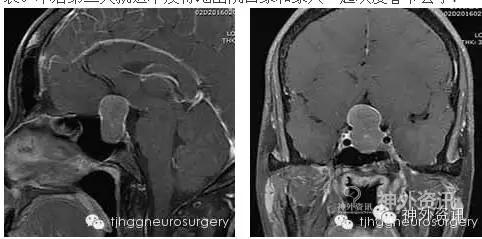

今年45岁王女士,擅长手工,爱织补,近日在家闲来织补衣裳,发现视力大不如前,穿针引线也需要孩子们帮忙了。子女们难得在家陪她,坚持带她到医院检查检查。一检查就发现脑袋里面长了个肿瘤,正好压迫视神经,导致视力下降。一家人忧心匆匆,坚持春节期间接受手术。

为了解除肿瘤对视神经的压迫,更为了解除肿瘤对患者及家人心理上的压迫,雷霆教授决定利用自己的休息时间,在麻醉科、手术室医护人员的精心保障下,行经单鼻孔-蝶窦入路肿瘤显微切除术,手术顺利。术后第一天王女士就说视力明显好转,可以清晰地看见来查房的雷教授的笑容,同时情真意切地说道:父母给了我生命,雷教授您给了我光明!感激之情溢于言表。术后第三天就迫不及待地出院回家和家人一起欢度春节去了!